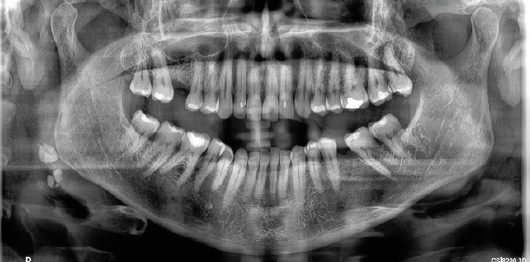

Métodos: Se llevó a cabo un caso clínico en una paciente de 40 años con fracaso de restauración fija dentosoportada en el incisivo central superior izquierdo, asociado a caries radicular subgingival con mal pronóstico restaurador. Tras la evaluación clínica y radiográfica, se indicó la exodoncia atraumática del diente afectado. Inmediatamente después, se realizó la colocación de un implante postextracción. El defecto periimplantario (gap) fue rellenado con un xenoinjerto óseo bovino. De forma simultánea, se llevó a cabo un injerto de tejido conectivo con el objetivo de optimizar el volumen y la estabilidad de los tejidos blandos periimplantarios. Se procedió a la colocación de una restauración provisional inmediata atornillada, diseñada para preservar el perfil de emergencia y guiar la cicatrización de los tejidos periimplantarios. Tras un periodo de cicatrización de cuatro meses, se colocó la restauración definitiva atornillada.

Resultados: El seguimiento clínico y radiológico evidenció una correcta osteointegración, estabilidad de los tejidos periimplantarios y un resultado estético satisfactorio, mantenido a los cuatro años.